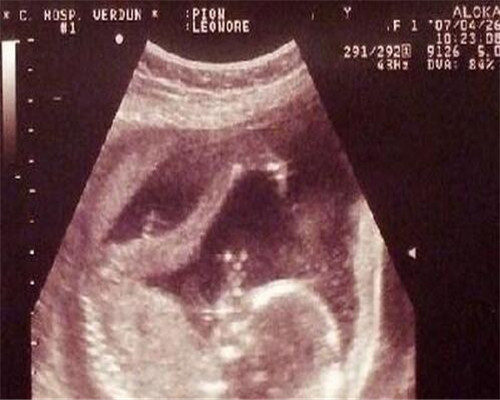

1、超声波扫描:超声波是一种声波,到目前为止的报告显示,它对胎儿没有不良影响,因此在妇产科界使用非常普遍。利用超声波诊断胎儿性别时,男婴的准确度可达95%以上,女婴的可靠度则只有85%左右。而且准确度还是B超师或者医生的经验有直接的关系

从b超数据看生男生女

从b超数据看生男生女?b超是孕妇在孕期里必做的检查项目之一,我们可以从b超的检查结果中查看胎儿的发育正常与否,而有些人甚至说可以从b超单上看出生男生女。下面,我们一起来看看。

11:长型孕囊为男孩,圆型孕囊为女孩?

事实真相:有人说,看B超单的数据也能看出男女。男孩子在怀孕两个月前的孕囊是长型的,女孩子是椭圆或是圆型。准妈妈们的孕囊看上去形状有所区别与胎儿性别没有关系。一般发育较好的孕囊是圆扁形的,但是有时孕囊会随宫腔的形状而变长。孕囊的形状由zg张力和含羊水量决定的,会自行改变形状。这样,怀孕天数不同,看到的孕囊也可能不一样。另外,每次B 超探头的方向不同,从不同的角度看,孕囊的形状也是不一样的。